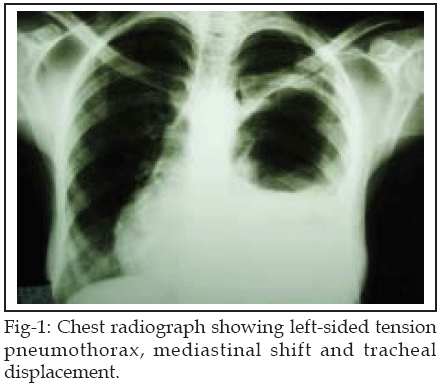

Chest radiograph taken on admission showed tension pneumothorax, mediastinal shift, and tracheal displacement (Fig-1). Echocardiography showed perforated hydatid cyst adjacent to pericardium (Fig-2). Electrocardiogram showed sinus tachycardia. The ultrasound scan confirmed a single 16-week viable fetus. Renal and hepatic function tests were normal. Indirect hemagglutination test for echinococcus was negative.

Pulmonary hydatid cysts are asymptomatic until they reach a large size and become complicated.2 A sudden rise in the intrapulmonary pressure is the usual precipitating factor in rupture of the cyst: the cause could be a trivial one such as coughing or sneezing, though sometimes it may follow an increase in intraabdominal pressure as in pregnancy. However rupture may occur spontaneously without any predisposing factor.5 The occurrence of tension pneumothorax because of the rupture of the hydatid cyst is a rare complication. The signs of tension pneumothorax include marked dyspnea, cyanosis, tachycardia and hypotension. The trachea is usually deviated to the contralateral side and the affected side of the chest demonstrates increased resonance to percussion and decreased air entry and breath sounds.6 In this case, chest radiograph and echocardiography were of great value in diagnosing the perforated pulmonary hydatid cyst adjacent to pericardium.